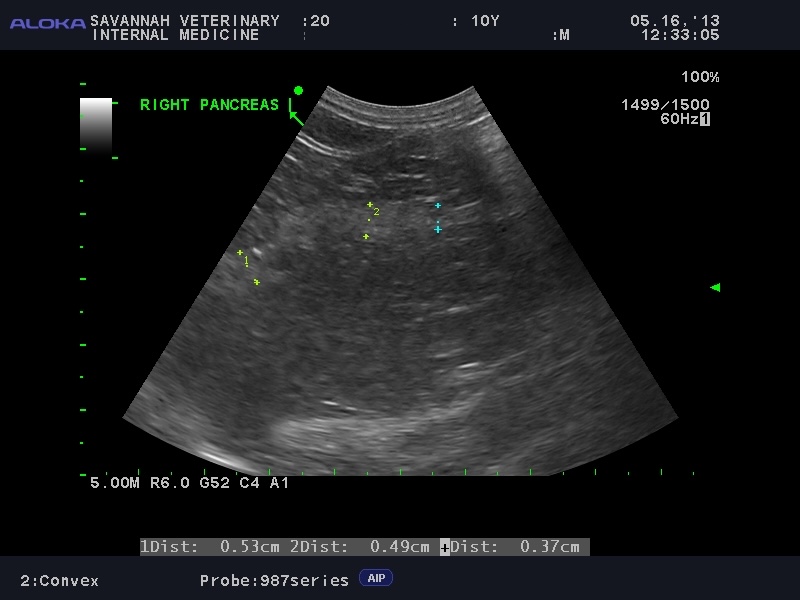

Visualizing The Pancreas: For the diagnosis of feline pancreatitis, an abdominal ultrasound is an important diagnostic tool. While X-rays are typically not very useful, ultrasound provides a non-invasive way to visualize the pancreas. The accuracy of ultrasound is highly dependent on the skill of the operator, as the pancreas can be difficult to locate and assess in cats. At Savannah Veterinary Internal Medicine, our team performs detailed ultrasounds to help identify pancreatitis, even in subtle cases. Even more so than the fPLI test, ultrasound may be normal in cats with mild, or chronic pancreatitis.

To illustrate this diagnostic challenge, the appearance of the pancreas on ultrasound varies significantly between different forms of the disease:

Acute vs. Chronic Feline Pancreatitis Ultrasound Images:

Recognize the varied imaging features of the inflamed feline pancreas, where acute and chronic forms present with distinct ultrasonographic changes.